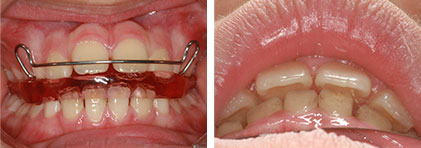

生長誘導性矯正

最常發生在換牙期間的小朋友,我們用專業的設備和技術預測控制將來牙齒的生長,與期說是預測,不如說是我們引導恆牙的生長,一步一步長在我們希望或預期的地方。